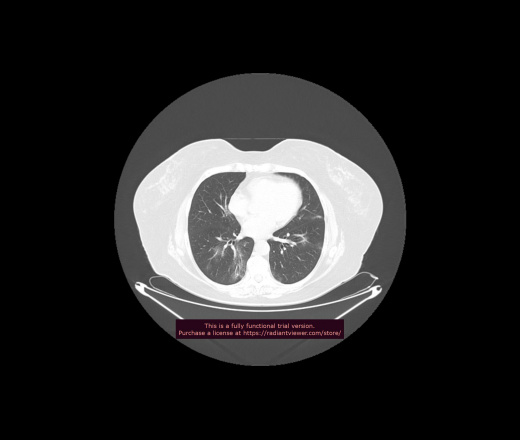

Уважаемые коллеги, если имеется интерес, сможете ли Вы спрогнозировать дальнейшее +-одинаковое течение процесса у 4 данных разных пациентов? Зацепиться где-то можно очень просто, где-то нельзя.